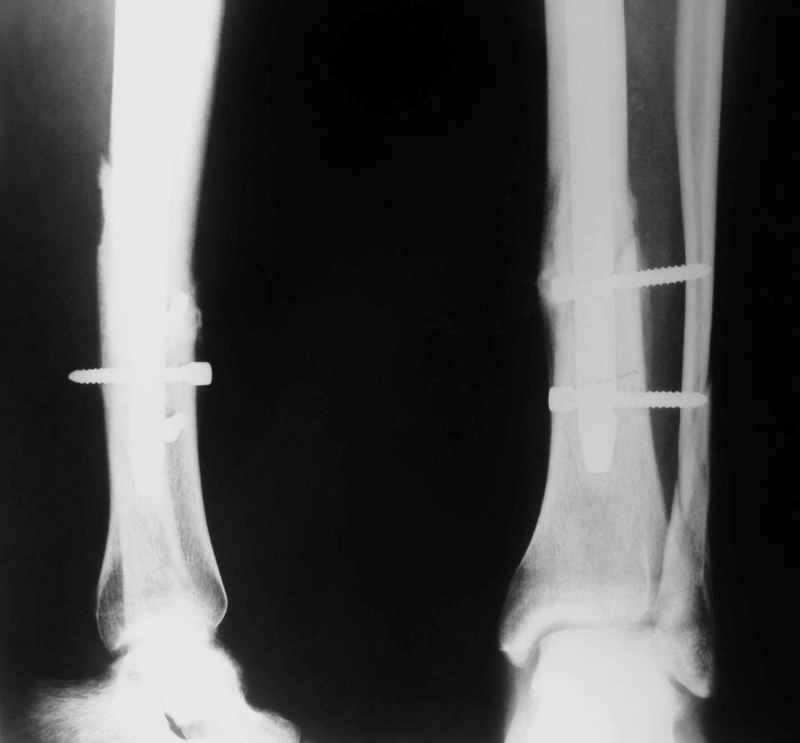

Потекли дистальные винты!

В дистальном отломке три винта( два медио-латеральных и один вентро-дорзальный).

Медио-латеральные вынты - мимо блокирующих отверстий фиксатора, вентро -

дорзальный винт - в отверстии.

Проблемы с верхним дистальным медио - латеральным винтом - он в линии перелома (

перелом косой).

Выполненный остосинтез нестабилен. Штифт надо заменить по "размеру" на солидный, дистльно три запирающих винта. Успехов!

Отправитель: Alexander Chelnokov 21 Январь 2005, 21:31

Перелом спиральный, то есть низкоэнергетический, так что со сращением дело обстоит уже неплохо, лишь бы "костоеда" не развилась. Отломки выглядят уже стабилизированными костной мозолью, так что довводить винты, наверно, уже незачем. Разве что при клинической оценке подвижность еще есть - тогда можно для стабилизации наложить простейший аппарат, не опасаясь контакта его элементов с гвоздем, поскольку места в дистальном метафизе оставлено более чем достаточно.

С Александром согласен, нет необходимости делать дополнительные усилия для сращения, не большая компрессия аппаратом из двух колец и полная нагрузка доделает работу.